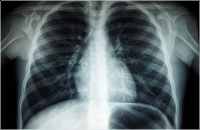

בעלה של המנוחה טוען כי רופא הריאות התעלם מממצא מחשיד, ובכך הצניח את סיכויי החלמתה בעשרות אחוזים: "צריך היה לבצע ביופסיה מיד"

איחור באבחון סרטן ריאה: משפחת המנוח תפוצה ב-2.1 מיליון ש'

על רקע טענת המשפחה שניתן היה לגלות את מחלת יקירם בשלב מוקדם יותר ובכך לשפר את סיכויי החלמתו - נחתמה פשרה עם המדינה, כבעלת ביה"ח שיבא, לתשלום פיצוי העתק